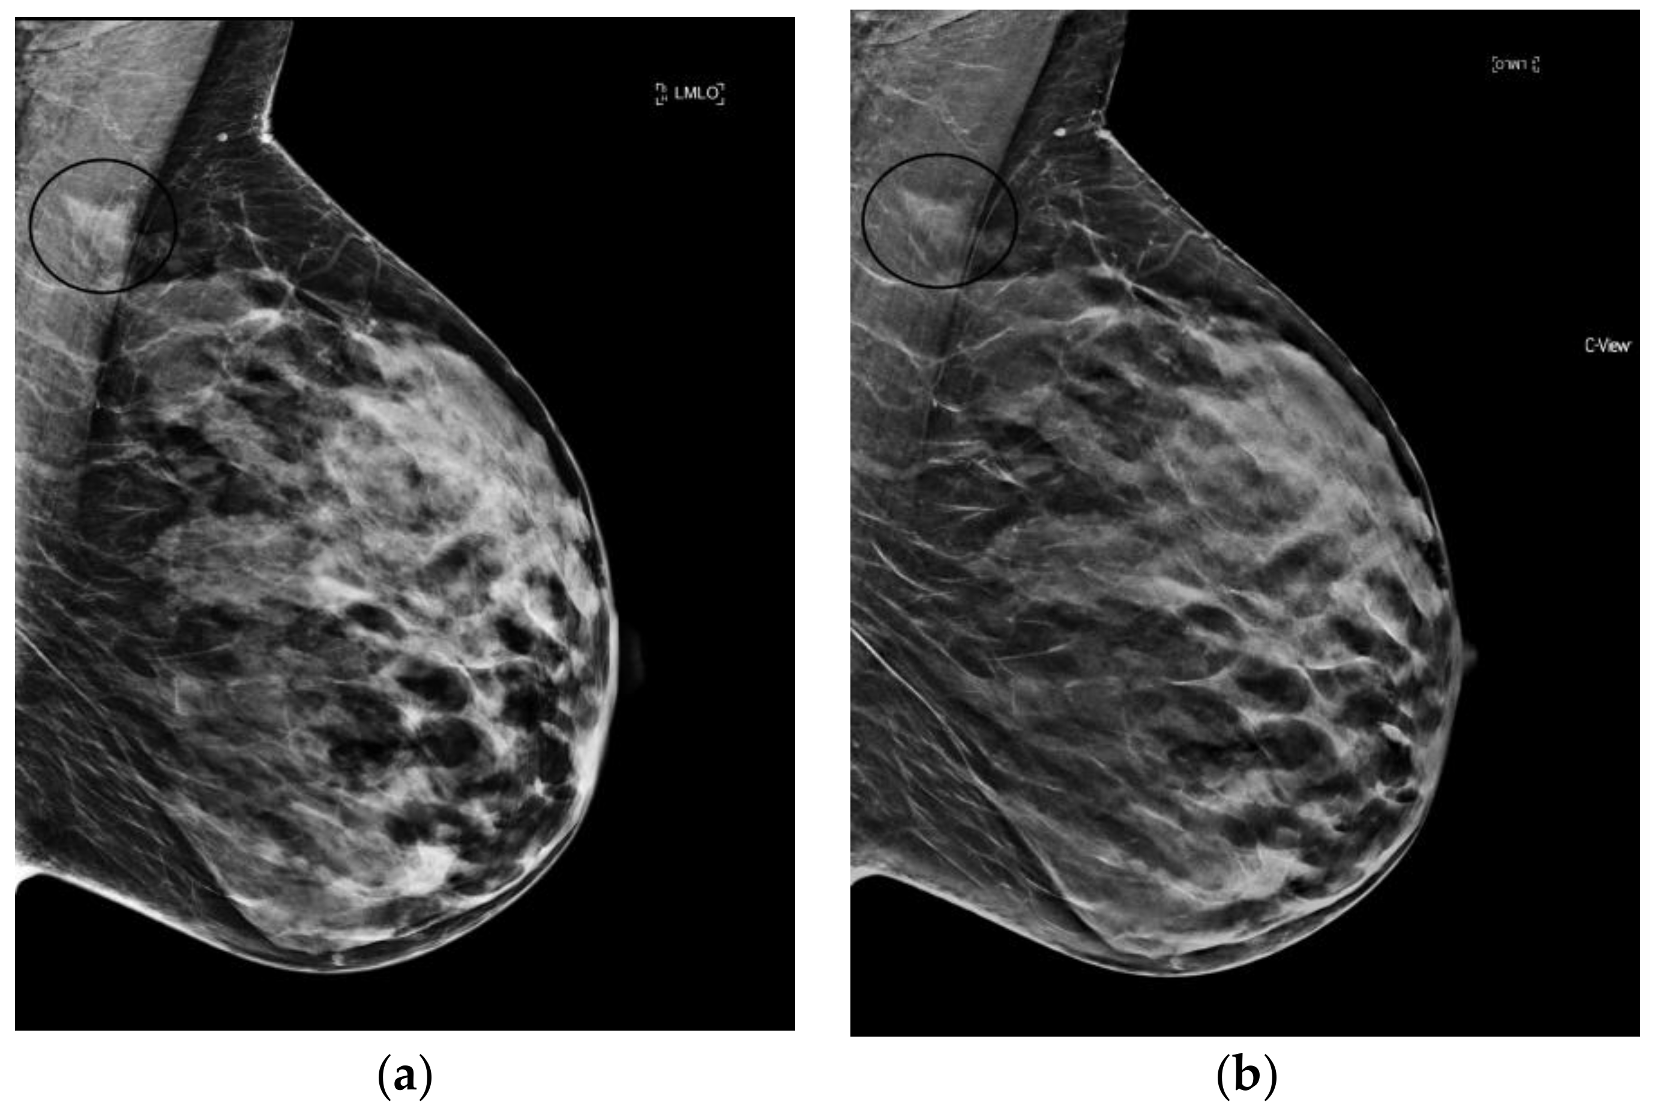

s2D+DBT was inferior to 2D+DBT and 2D FFDM alone for detection of microcalcifications and DCIS in the 11-20mm range in the TOMMY trial [32]. And specificity for calcifications has been shown to be lower compared to masses and asymmetries for both s2D and 2D FFDM [33]. Despite this, in situ cancer detection was not affected by decreased recall rates for calcifications in Freer’s study [31]. Furthermore, Choi et al. showed similar performance of s2D and FFDM in detection of calcified and non-calcified stage T1 cancers [34]. How synthesized mammography definitively affects the rate of cancers detected as calcifications remains to be fully validated. (Figure 2).

Figure 2.

Linear, heterogeneous calcifications (circled in black) best seen on synthesized mammography images (grade 2 ductal carcinoma in situ). (a) 2D FFDM (b) s2D (c) s2D zoom.